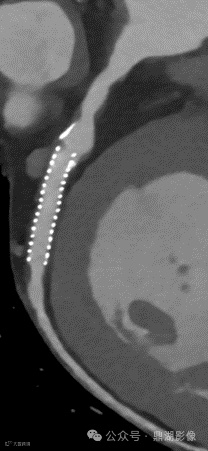

UHR超清模式成像,可更清晰地呈现支架管腔及斑块轮廓,大幅提升血管支架和软斑块的评估能力。

联影光子计数能谱CT-uCT Ultima搭载业内最新一代0.2 mm像素光子计数探测器,实现全身各部位的全准直超清(UHR)成像,呈现业内领先的空间分辨率和卓越细节再现能力。AI重建算法进一步优化图像质量,有效克服光子计数探测器带来的信噪比下降问题,在保持超高清分辨率的同时实现低噪声与低剂量。借助高速数据传输与智能处理能力,uCT Ultima可在最高系统转速和最宽探测器覆盖下同步实现UHR与能谱成像,无需在空间分辨率和能谱信息之间做出取舍,使光子计数CT优势全面释放。